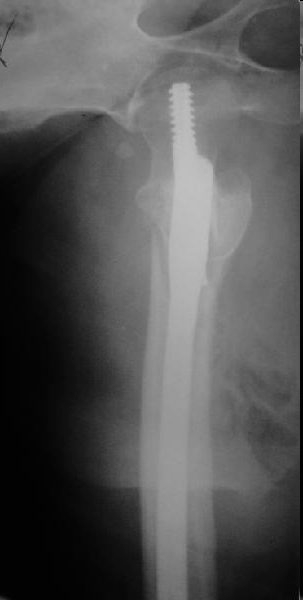

Re: Чрезподвертельный перелом бедра. Остеосинтез стержнем. Перелом металлофиксатора. Дальнейшая тактика?

Это типичная проблема, вот аналогичный случай. Удалили, исправили, фиксировали другим PFN.